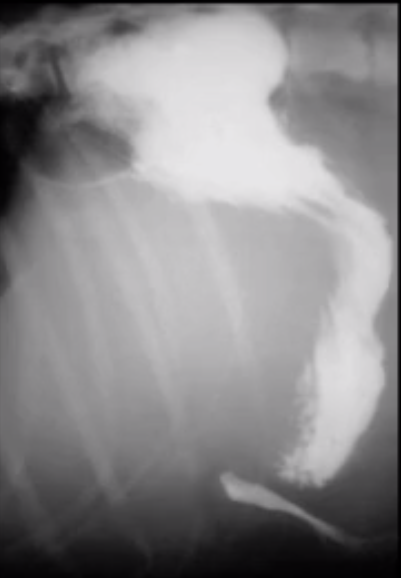

What does this image show?

Displacement of stomach by hepatic mass?